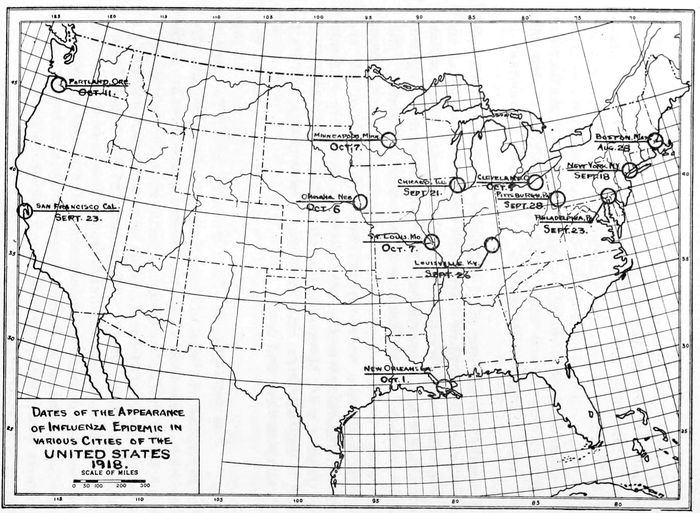

Dates of the Appearance of Influenza Endemic in various Cities of the UNITED STATES

1918.

In the city of Boston during the week ending August 28, at the Naval Station at the Commonwealth Pier, 50 cases of influenza occurred and within the next two weeks more than 2,000 were reported in the naval forces of the First Naval District. Of these 5 per cent. developed broncho-pneumonia with a mortality of more than 60 per cent. From here it probably spread to Camp Devens and thence ran rapidly over the country. There can hardly be a question that it spread along the lines of traffic. Up to November 9 there were reported 3,339 cases among the civilian population of Boston. There were 3,430 deaths from influenza, the presumption being that these were due to bronchial pneumonia, although not reported as such. The deaths from all forms of pneumonia were reported as 942, making in all 4,372 deaths from September 7 to November 9. This discrepancy—that is more deaths than reported cases of influenza—is due to the fact that influenza was not made a reportable disease until the date of October 4, fully a month from the time the epidemic appeared. The weather conditions were generally fair and no noted abnormality is recorded as compared with other years. The statement of the Health Department of this city was that, after a practical disappearance of influenza in October, there was a slight recurrence in November and a more pronounced recurrence about the first of December, since which time the cases have slowly but steadily decreased, until at present—December 21—the fatalities attributable to influenza are about 20 daily.

In the city of New York the epidemic first appeared September 18. Up to and including December 27 there were reported to the Department of Health 136,061 cases of influenza and 21,388 20cases of pneumonia. The number of deaths since September 18 was 11,725 attributed to influenza in the death certificates filed in the Health Department and 11,601 attributed to pneumonia. The epidemic reached its peak during the week of October 19, slowly subsided and was practically at an end on November 9. While the epidemic is reported as ending on this date, the mortality rate from influenza and pneumonia is still very much above normal. No particular features concerning the meteorological conditions were noted, except that in this city the weather was clear and delightful during the months of September and October when the epidemic was rampant.

In the city of Philadelphia on July 22 the Health Department issued its first health bulletin on so-called Spanish influenza, announcing the possible spread of this disease into the United States. On September 18 a warning was issued against an epidemic, the department starting a public campaign against coughing, sneezing and spitting. On September 21 the Bureau of Health made influenza a reportable disease. At this time the authorities stated an epidemic of influenza was recognized as existing among the civil population of similar type to that found in the naval stations and cantonments; that a large percentage of cases was accompanied by pneumonia; that patients should be isolated and attendants wear masks; that isolation be practiced for a period of ten days after recovery to prevent carriers; that patients be guarded against relapse and that the public be cautioned against large assemblages and crowded places, as well as to avoid coughing, sneezing and spitting. On October 3 the churches, saloons and theatres were closed, funerals were made private and food handlers were required to protect their wares. The number of cases reported from September 23 to November 8 was 48,131, but the Bureau states, from a rough estimate, the number of cases was probably 150,000. The total number of deaths reported was 7,915 from influenza and 4,772 from pneumonia in all its forms, the presumption being that the deaths during this period were due to influenzal pneumonia. The weather condition during this time is recorded as mild and fair.

The influenza cases began to be reported in Cleveland on October 5, and up to December 20, 22,703 cases had been recorded. Certificates recording deaths due to influenza alone numbered 2,497, while pneumonia amounted to 833. The epidemic was at 21its height in the latter half of October and the weather was spoken of as pleasant fall weather. During the week of October 26 the epidemic reached its greatest height, abated in the week ending November 23, increased later, but showed a drop for the week ending December 21.

The epidemic first reached Chicago on September 21, and from that date on it rapidly increased throughout the city for a period of 26 days until October 17, when it reached its maximum both in the number of deaths from influenza and from pneumonia. On that day the total number of deaths from influenza and from pneumonia reported was 2,395. From September 21 until November 16 there were reported 37,921 cases of influenza and 13,109 cases of pneumonia. On September 8 at the Great Lakes Naval Training Station, which is 32 miles north of the city, an extensive outbreak of influenza occurred. This was 13 days before the outbreak in the city of Chicago itself. Camp Grant, located at Rockford, 92 miles northwest of the city, suffered an outbreak on September 21. A suggestion of the likelihood that influenza was prevalent in this country in a mild and unrecognized form in the spring of this year is shown by the fact that numerous local outbreaks of acute respiratory diseases were brought to the attention of the Health Department of Chicago. These occurred especially in large office buildings and in industrial departments. The total number of deaths from influenza and pneumonia during 14 weeks was 51,915. This would indicate that a very great number of cases were not reported to the Bureau of Health until they died or else there must have been a large number of deaths due to lobar pneumonia. One naturally obtains from these figures the impression that the disease was not recognized for a long time, that the pneumonia must have been called lobar pneumonia, and that the actual figures gathered by this city, as well as others, must have been greatly confused at the onset of the epidemic. It is not unlikely that records from many of the army cantonments and naval stations may be considered from the same viewpoint. Weather conditions were considered normal at the height of the epidemic, the weather being dry. There has been a flare-up of influenza recently, but not in sufficient numbers to justify calling it epidemic.

In the city of Louisville, Ky., the epidemic started September 26, and the total number of cases up to December 21 is reported 22as being 9,445. Out of this number 772 deaths occurred from pneumonia. No distinction is made here between broncho-pneumonia and lobar pneumonia, but the presumption from the records of other cities at this time is that these were cases of broncho-pneumonia following influenza. The weather was described as being delightful fall weather. The statement is made by the authorities that while the epidemic is still prevalent, it is confined largely to children and is rapidly abating.

The first case in the city of St. Louis was reported about October 7, and up to December 23 there had been 31,531 cases reported to the Bureau of Health. They recorded 1,920 deaths with influenza given as a contributing cause. Preceding the time when the epidemic was at its height the weather was fair and warm, and the statement is made that, “without going into the matter exactly, we have been of the opinion that damp, rainy weather has been a help in controlling the disease.” The opinion was expressed by the Commissioner of Health that the disease had now abated.

No information could be obtained as to when the epidemic first reached the city of New Orleans, but during the months of October and November 43,954 cases of influenza were recorded. Of this number 2,188 died from a combination of influenza and pneumonia. They stated in their health report that during the period from January 1 to December 31 there were 239 deaths attributable to broncho-pneumonia. The weather was mild and on December 24 the epidemic was stated to have abated.

The city of Minneapolis recorded its first case on October 7, but the authorities expressed their belief that a few cases had appeared before that date. Up to December 21, 15,000 cases had been reported to the Bureau of Health and of these there had been 735 deaths from broncho-pneumonia. They had in their city a late, rainy fall and up to that period they had had no cold weather.

The record obtained from the city of San Francisco stated that the epidemic first appeared September 23 and that it was very widespread in that city early in October. There were two invasions and 53,260 cases reported. At the height of the epidemic more than 2,000 cases were reported in one week; 188 deaths occurred from influenzal pneumonia. The following week, after the institution of mask wearing, in which between 80 and 90 per cent. of the population concurred, it was stated that the number 23of cases decreased to about 200. It was stated that the weather was generally very fair during the epidemic.

From the city of Portland, Oregon, the following information was obtained: The epidemic first appeared October 11, with a second one toward the end of the year. There were 8,079 cases reported, with 658 deaths from influenza and 250 from pneumonia. Weather conditions were stated to be varied, but the health officer believed that during the worst wave the weather was clear and dry, with easterly wind. He believed that a decrease in influenza was noticed immediately after a Chinook wind and warm rain. Similar observations were made by Coutant in Manila.